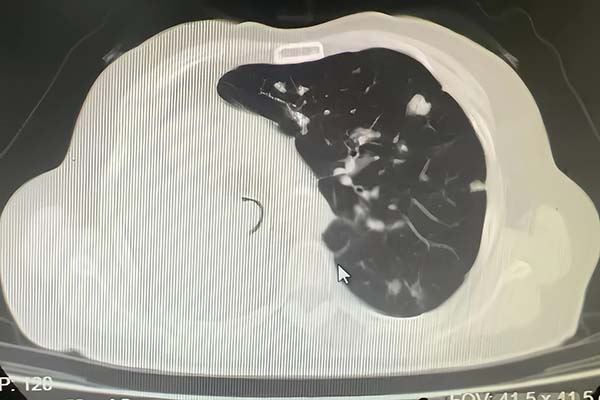

患者为老年女性,有右肺肿瘤病史1年余,近5个月出现活动后喘息,5天前症状急剧加重,出现呼吸急促、不能平卧等危急情况。患者既往有冠心病、高血压、脑梗、糖尿病等多种基础疾病。外院CT显示其气管下段被肿瘤阻塞,仅存一条缝隙,右肺完全不张,左肺存在多发转移灶,病情十分危重。由外院转诊至垂杨柳医院呼吸与危重症医学科。

▲患者胸CT提示气管仅留一条缝隙

患者入院时高枕卧位,呼吸急促,伴三凹征,心率120次/分,血气分析提示伴有II型呼吸衰竭,外院携带CT提示气管下段肿物阻塞,仅留一条缝隙,右肺完全不张,左肺多发转移灶。